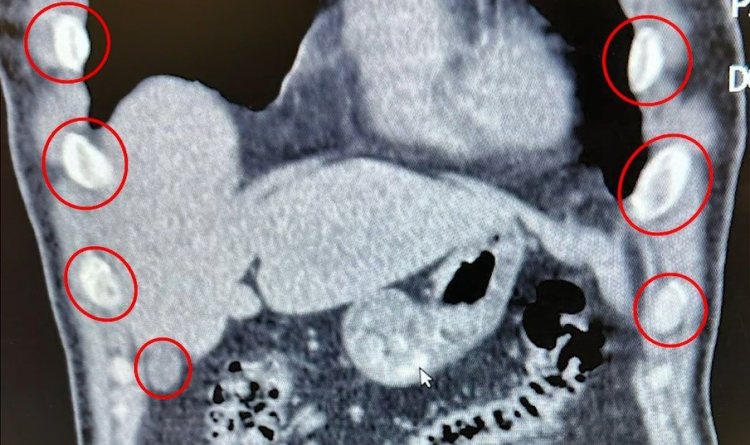

Bitlis İl Emniyet Müdürlüğü Narkotik Suçlarla Mücadele Şube Müdürlüğü ekipleri, uyuşturucu ile mücadele kapsamında önemli bir operasyona imza attı. Tatvan ilçesinde durdurulan bir otobüste yolcu olarak seyahat eden yabancı uyruklu 2 kişi gözaltına alındı. Şahısların yapılan tıbbi müdahalesinde, yuttukları 136 kapsül halinde toplam 1 kilo 48 gram metamfetamin ele geçirildi.

Bitlis’te düzenlenen narkotik operasyonunda yabancı uyruklu iki şüpheli, midelerinde taşıdıkları 136 uyuşturucu kapsülleriyle yakalandı.